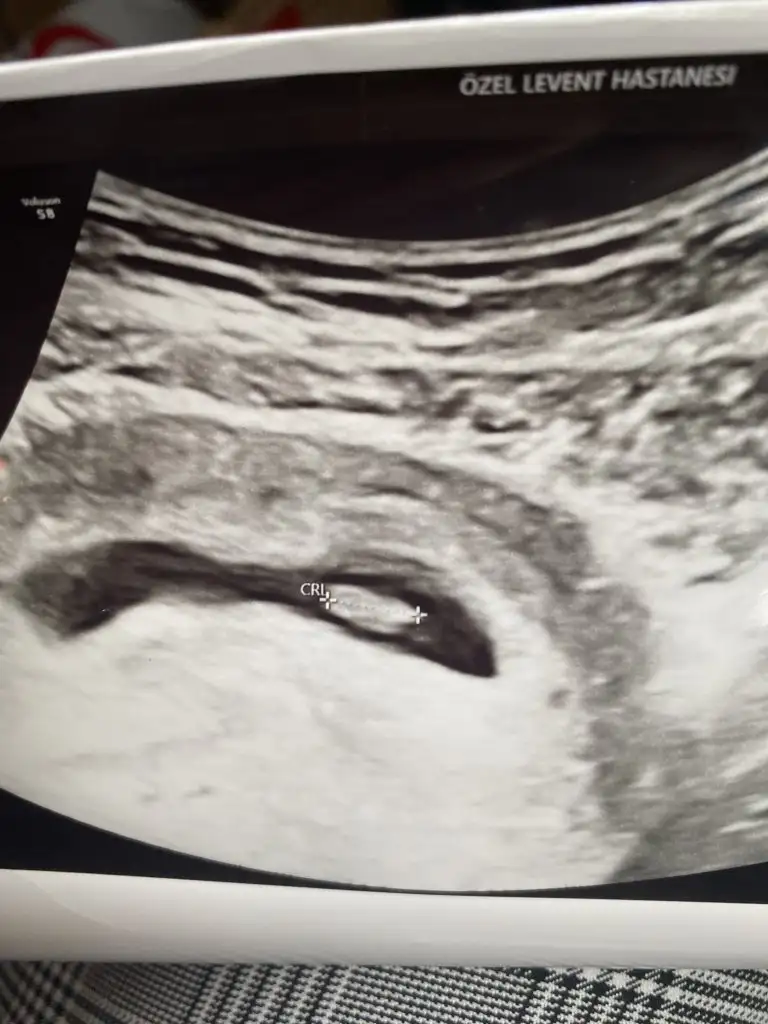

Evet banada öyle dedi 2 hafta uzun geliyor ama hemen de bitiyorKizlar sizde keseyi gördükten sonra 2 hafta sonraya mi randevu aldınız.yani bu doktorun öngörüsü. Bu süreçte bir sikinti olmazsa gidilmiyor dimi.nedense süre bana uzun geliyor aşamalarını bilsemdeonce kese snra kese icinde bebek sonra kalp atisi bekleyeceğiz.

Banada dün 2hafta sonra gel dedi ama 3hafta sonra mı gitsem diye düşünüyorum ben. Daha garantiye almak istiyorum sanırım. 7+ olsunKizlar sizde keseyi gördükten sonra 2 hafta sonraya mi randevu aldınız.yani bu doktorun öngörüsü. Bu süreçte bir sikinti olmazsa gidilmiyor dimi.nedense süre bana uzun geliyor aşamalarını bilsemdeonce kese snra kese icinde bebek sonra kalp atisi bekleyeceğiz.

Canım biz keseyi gördük 10 gün kontrol süresi dolmadan yine gel dediKizlar sizde keseyi gördükten sonra 2 hafta sonraya mi randevu aldınız.yani bu doktorun öngörüsü. Bu süreçte bir sikinti olmazsa gidilmiyor dimi.nedense süre bana uzun geliyor aşamalarını bilsemdeonce kese snra kese icinde bebek sonra kalp atisi bekleyeceğiz.